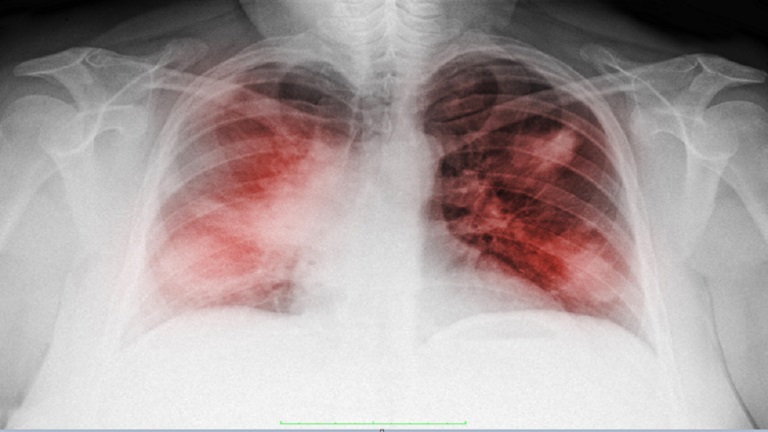

تشمل أعراض سرطان الرئة صعوبة التنفس والصداع وآلام الصدر المستمرة. ولكن قد يتعرض الفرد أيضا لخطر الإصابة بالورم إذا طور أيا من هذه العلامات غير العادية.